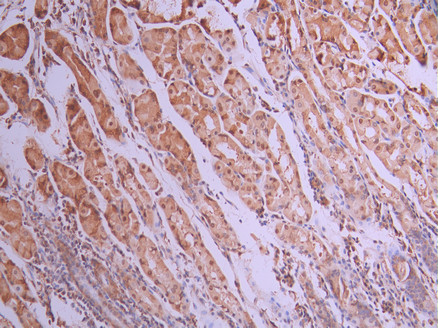

IHC image of CSB-RA821323A0HU diluted at 1:100 and staining in paraffin-embedded human stomach tissue performed on a Leica BondTM system. After dewaxing and hydration, antigen retrieval was mediated by high pressure in a citrate buffer (pH 6.0). Section was blocked with 10% normal goat serum 30min at RT. Then primary antibody (1% BSA) was incubated at 4°C overnight. The primary is detected by a Goat anti-rabbit polymer IgG labeled by HRP and visualized using 0.05% DAB.